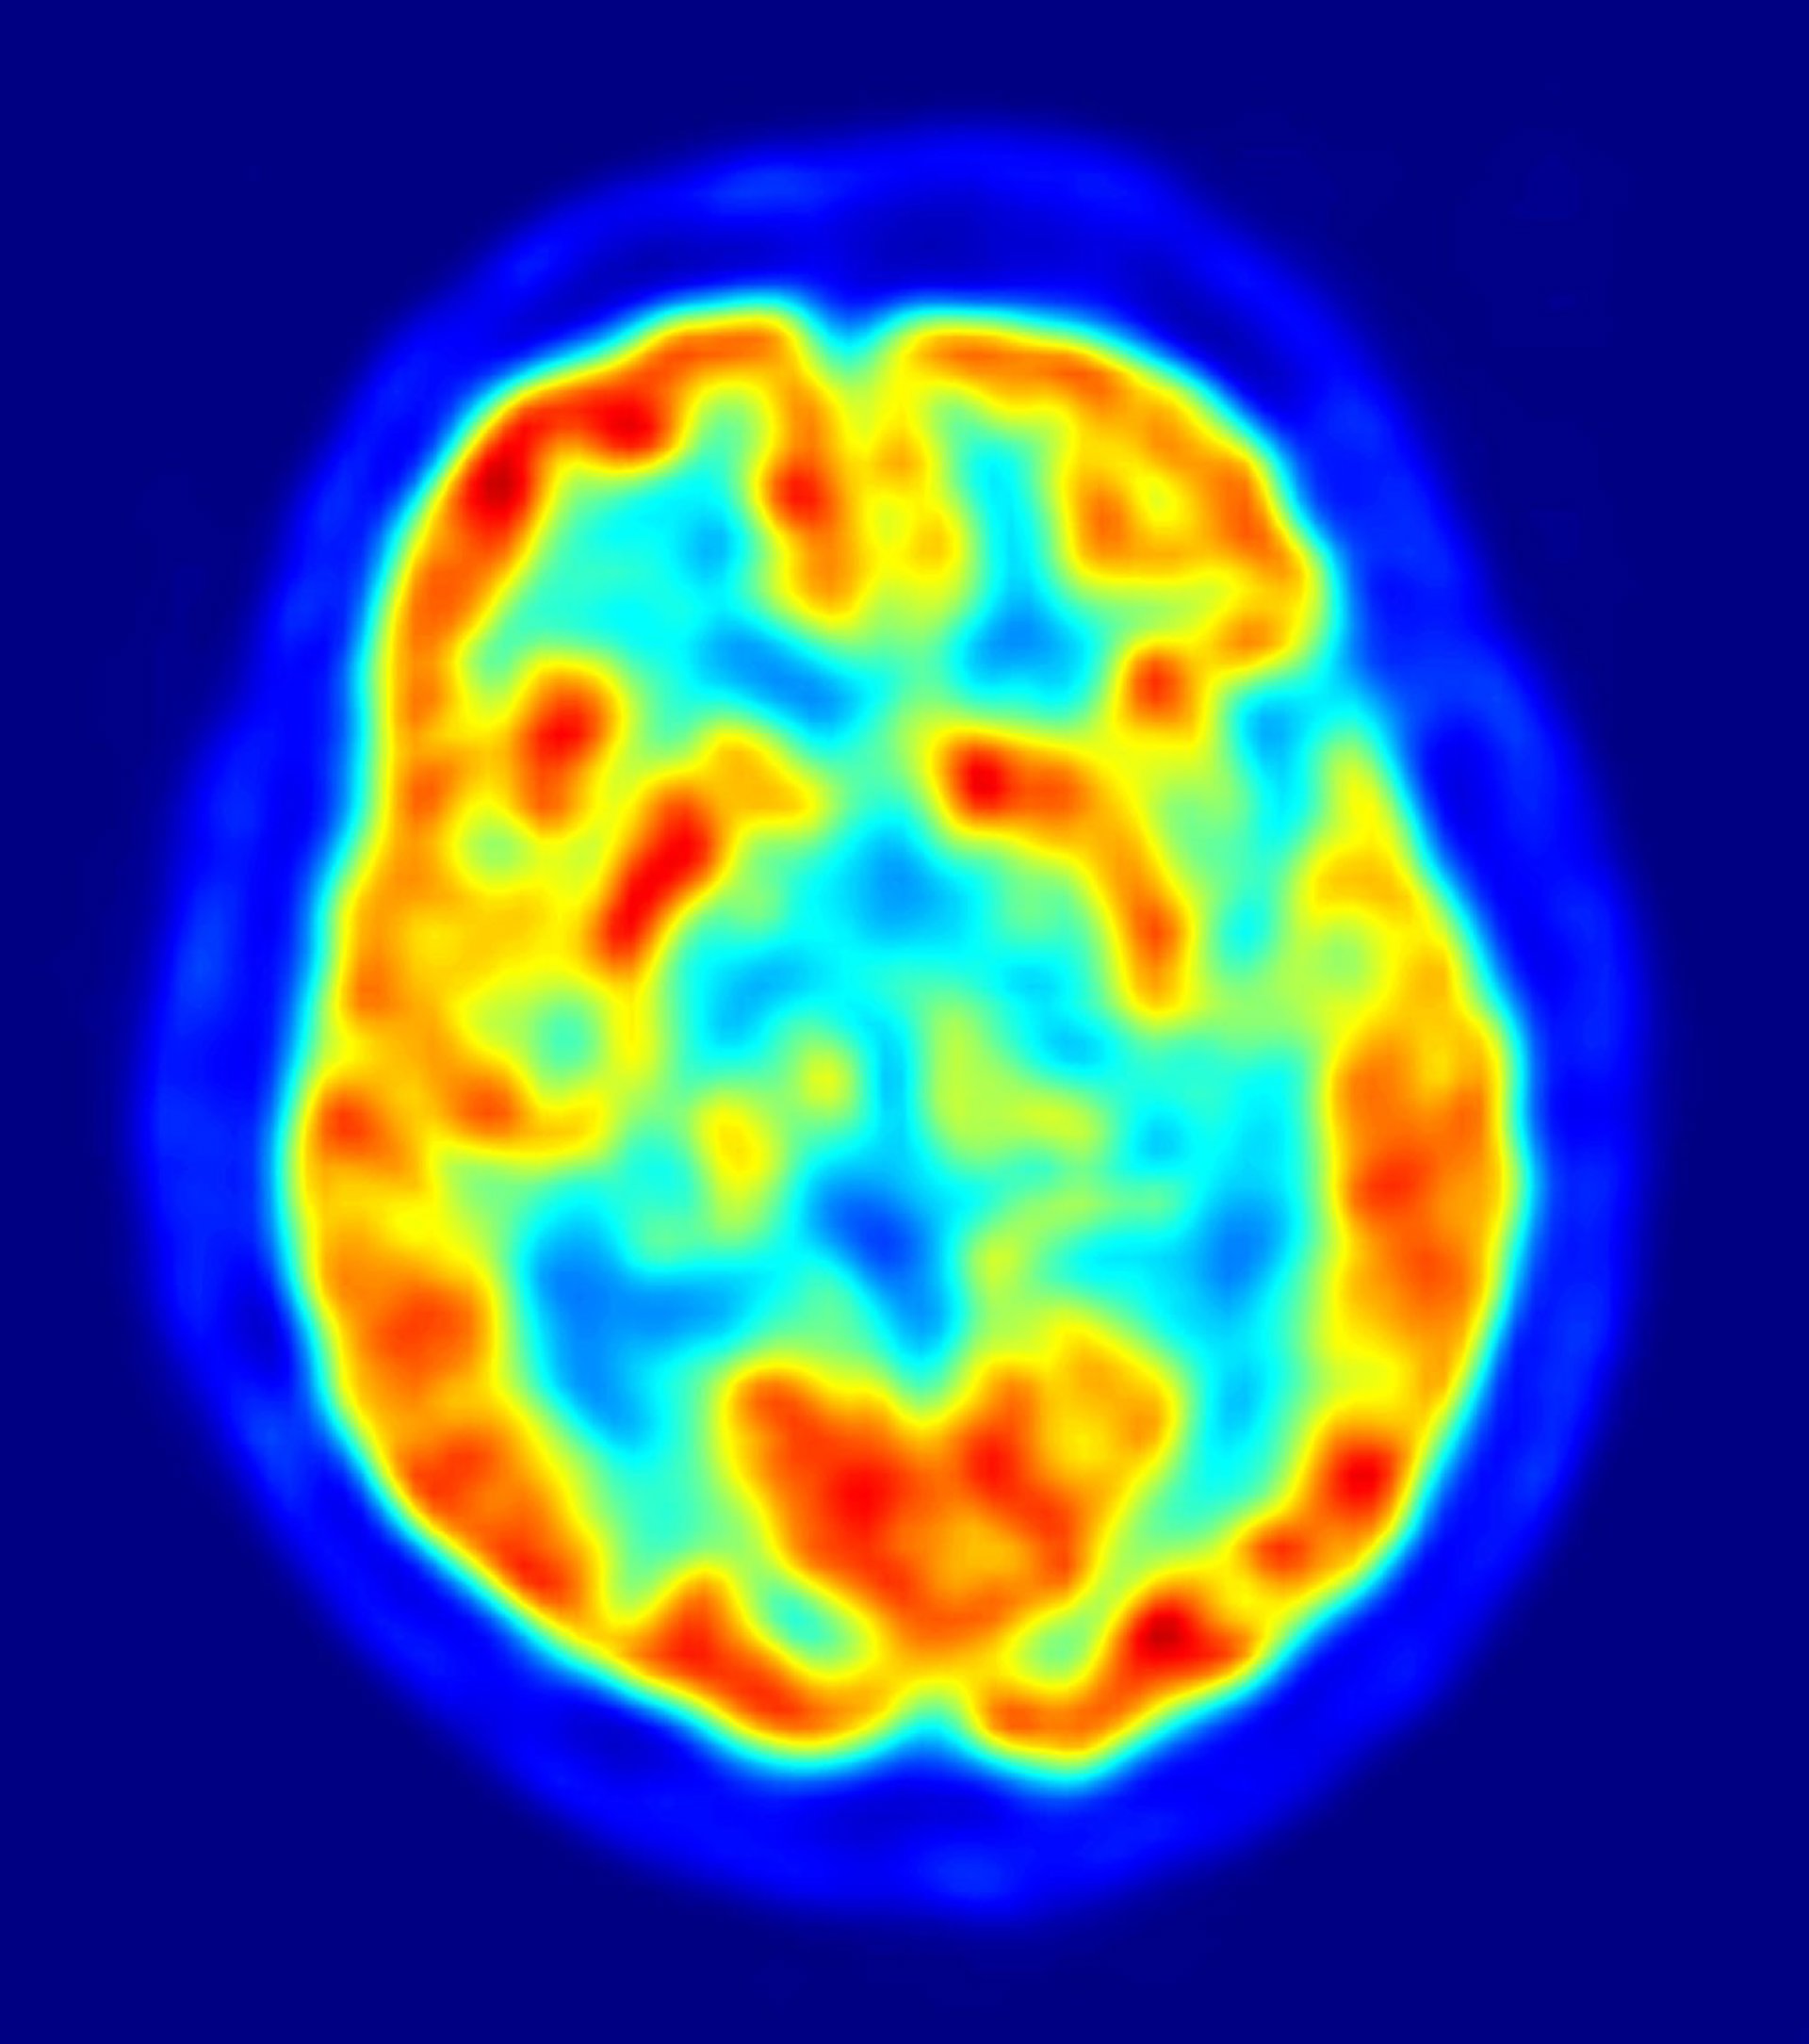

cerebro, recurso, neuronas

Los biólogos analizaron 12 regiones del cerebro, responsables de la conducta social y la toma de decisiones, en 88 especies de vertebrados, incluyendo aves, mamíferos, reptiles, anfibios y peces. Los científicos examinaron, específicamente, la actividad genética en dos redes neuronales: la red responsable de evaluar la importancia relativa de los estímulos (el sistema de recompensa mesolímbico), y la red responsable de la conducta social. La primera red mencionada es relevante en la adicción a las drogas y en el amor romántico -que se manifiesta en el cerebro de forma parecida a la adicción a las drogas. "En estas regiones clave del cerebro, encontramos una notable conservación de la actividad genética en las especies", apunta Hofmann.